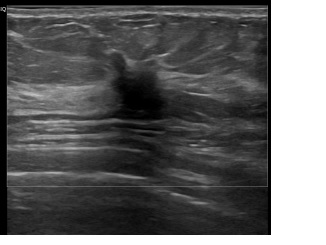

상기환자는 외부건진이상소견 조직검사위해 내원하신 50대 초반

여성분으로 의심스러운 좌측혹 조직검사 시행해 유방암 진단되었습니다.